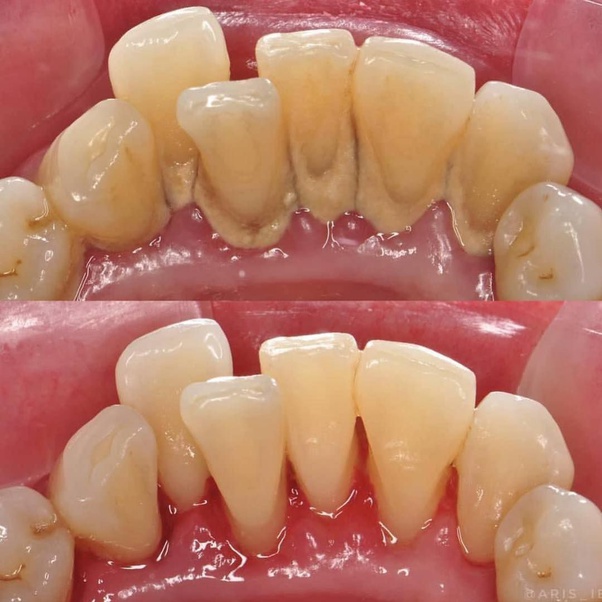

Her turning point came during a routine visit to her dentist, Dr. Mehta. He suggested a simple yet effective solution scaling and polishing. Priya was intrigued. She had heard about these procedures but never really understood their impact. Dr. Mehta explained that scaling and polishing are essential dental procedures designed to remove tartar, plaque, and stains from teeth, leaving them clean and smooth.

Determined to reclaim her smile, Priya scheduled an appointment. The procedure was straightforward, involving a thorough cleaning of her teeth to remove all the unwanted buildup. It was painless, and the results were immediate. As Priya looked in the mirror, she couldn’t believe her eyes. Her teeth were gleaming, and she felt a sense of rejuvenation she hadn’t thought possible.